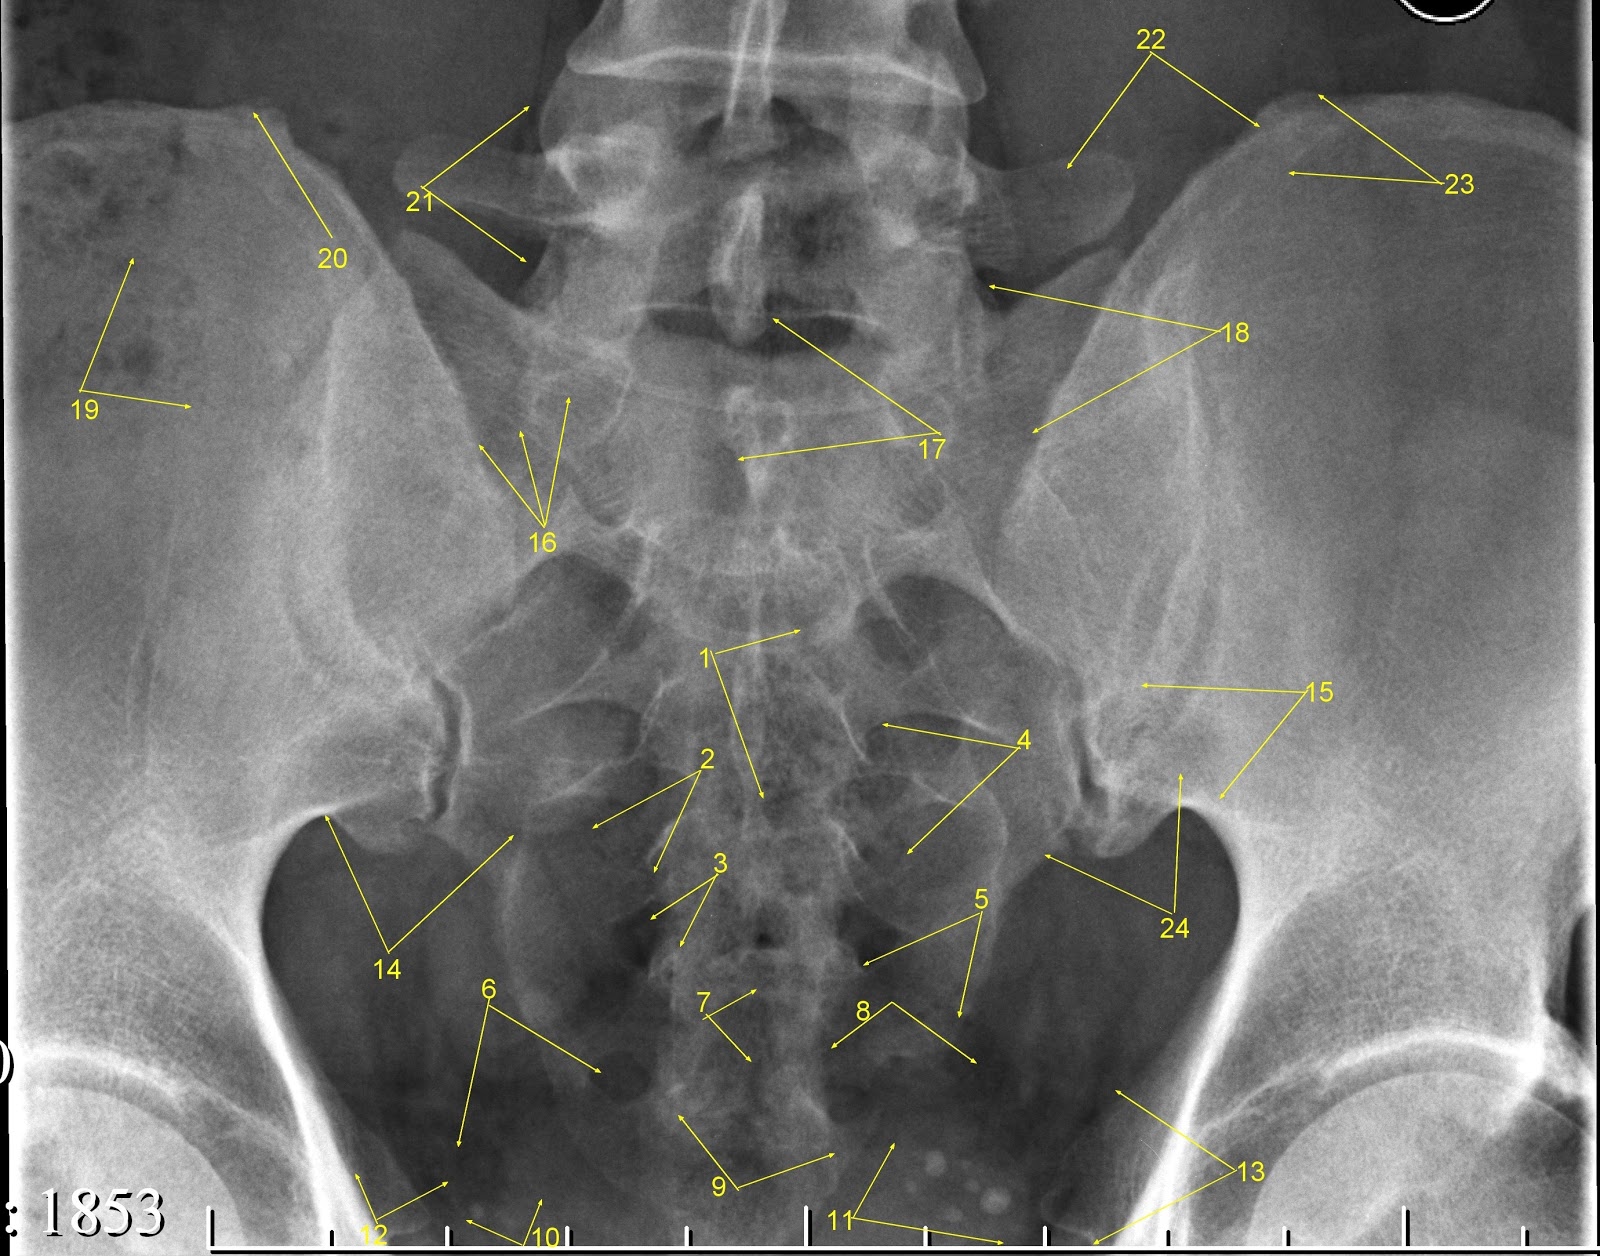

Рентгеновские снимки крестцово-копчикового отдела позвоночника